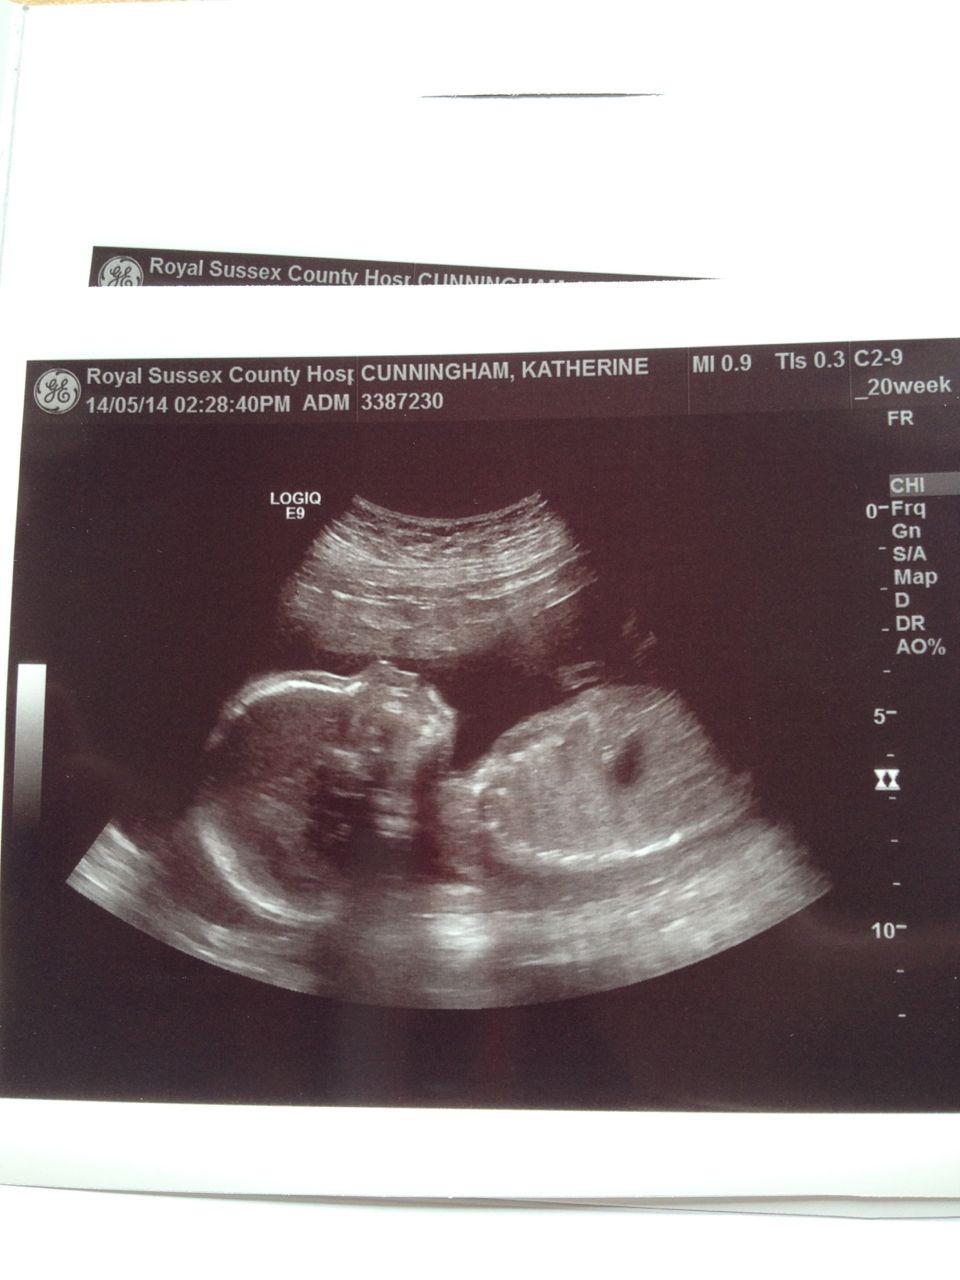

It’s been a revealing day, we had the latest scan showing us for about 20 minutes the wonder of a squirmy wriggling baby inside me. We marveled, grins on faces, chuckling and laughing at hands in front of a tiny face as if to say, no pictures please, and can you stop the poking lady? We saw blood pumping around a tiny body, and the crazy weird strangeness of watching a heart beat fast and strong. There is life inside me.

And we saw what we’d seen once before, unmistakable proof that yes we are bringing another boy into this world. A world of emotions to process today. We probably aren’t going to have any more children after this and so we come to understand we won’t nurture a girl through this world. We will instead nurture two boys, who no doubt will be very different from each other and who we get to teach how to live this life well. Part of me wants to rush out and read Steve Biddulph’s book on raising boys which seems to be a classic on the subject but that can maybe wait a few days.